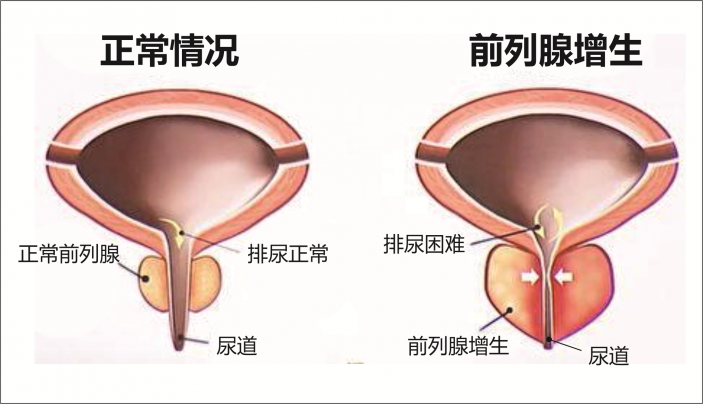

治前列腺增生不動刀,一根微導管讓它“由大變小”

衆所周知前列腺增生是困擾中老年男性的常見病,傳統的治療主要采用前列腺電切術。但是有的患者不願意切除前列腺,也有的患者因合并有其它疾病不能采用電切術治療。那麽,還有沒有其它的技術能夠治療呢?

我院這項“很牛”的技術——介入下前列腺動脈超選擇栓塞術,能讓前列腺增生“由大變小”。該技術無須切開任何組織,僅通過股動脈穿刺置入微導管,經動脈的自然腔道,送達前列腺動脈,将PVA材料置于雙側前列腺動脈即可完成手術。其原理是阻斷前列腺營養供給,使其逐漸萎縮變小,從而解除對膀胱、尿道的壓迫,達到治療的目的。

該名來自梅塘鎮的62歲患者有前列腺增生多年,2年前就希望通過手術治療,無奈血糖始終控制不理想,不能電切手術治療。近期患者因排尿困難加重來院,經查仍有手術禁忌症,不适宜采用電切手術。爲了幫助患者擺脫疾病的困擾,李旭丹團隊決定給予采用“介入下前列腺動脈栓塞術”治療。

“介入下前列腺動脈栓塞術”沒有特别的禁忌症要求,無需切除前列腺,不影響前列腺的腺體神經,且比傳統微創手術更微創,适合合并有其它疾病,不能行前列腺電切術的患者。